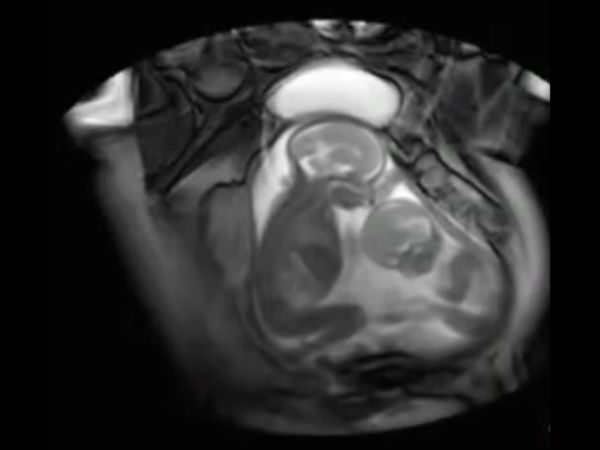

இரட்டையர்கள் பார்ப்பது என்றாலே ஆச்சரியமும், வியப்பும் தான். அதுவே அவர்கள் கருவில் அடித்து விளையாடுவதை பார்ப்பது என்றால்? இந்த காணொளிப்பதிவில் பாருங்கள்.

தாயின் கருவறையில் இருக்கும் இரட்டை சுசுக்கள், கருவில் வளரும் போதே ஒருவரை ஒருவர் அடித்து உதைத்து விளையாடி கொண்டிருப்பது போன்று காட்சிகள் கொண்டிருக்கிறது இந்த காணொளிப்பதிவு.

இந்த வீடியோ ஸ்கேனிங் செய்த பொது பதிவு செய்தது போன்று இருக்கிறது.

இந்த காணொளிப்பதிவில் இரட்டையர்கள் இருவர் அடித்து விளையாடுவது. ஒருவரை ஒருவர் மாறி, மாறி அடிக்க முயல்வது மிக தத்ரூபமாக இருக்கிறது. பிறந்த பிறகு அல்ல, கருவறையிலேயே நாங்கள் எங்கள் சுட்டித்தனத்தை துவங்கிவிட்டோம் என கூறுவது போல இருக்கிறது இந்த காணொளி.

இந்த காணொளிப்பதிவு உண்மையாகவே ஸ்கேனிங்கின் போது பதிவு செய்யப்பட்டதா? அல்ல கிராபிக்ஸ் உதவியால் உருவாக்கப்பட்டதா? என்ற கேள்விகள் மனதில் எழுந்தாலும். கருவில் வளரும் இரட்டையர்கள் ஒருவருடன் ஒருவர் விளையாடுவது உண்மையே என்கிறது அறிவியல்.